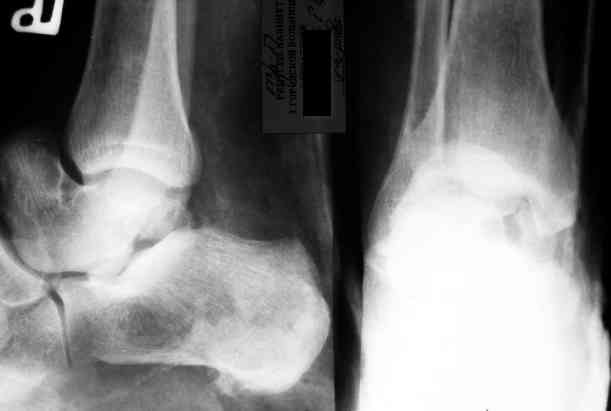

Уважаемый Александр! Как обещал представляю Р-граммы и операционные фото.

Ваши (лично ваши) рекомендации - астрагалэктомия-аппаратный пяточно-большеберцовый артродез с одновременным удлинением голени - правильно?

Да.

Мы обычно удлиняли на 2 уровнях по 1,5-2 см. В конце концов, можно и не удлинять, укорочение компенсировать вкладками в обувь.

Вместе с аваскулярным куском кости устранится субстрат. Надо опасаться не мягких тканей, а плохо кровоснабжаемых. Если после удаления тарана добиться контакта хорошо васкуляризованных пятки и больщшеберцовой, мягкие ткани не давить, чтобы некроза раны не было, то все должно зажить.